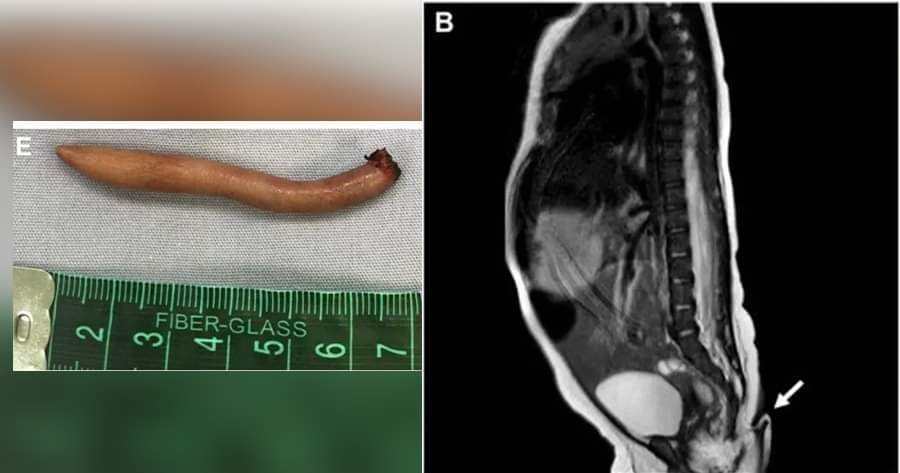

Luego de la valoración, determinarón que debía extirparse, por lo que anestesiaron a la bebé y le retiraron la cola en un proceso que no tuvo complicaciones.

Aunque sería el primer registró de este tipo en México, en Latinoamérica hubo un caso en Brasil. Allí médicos reportaron un niño que nació prematuro de 35 semanas por vía vaginal, el cual tenía una cola de 12 centímetros.